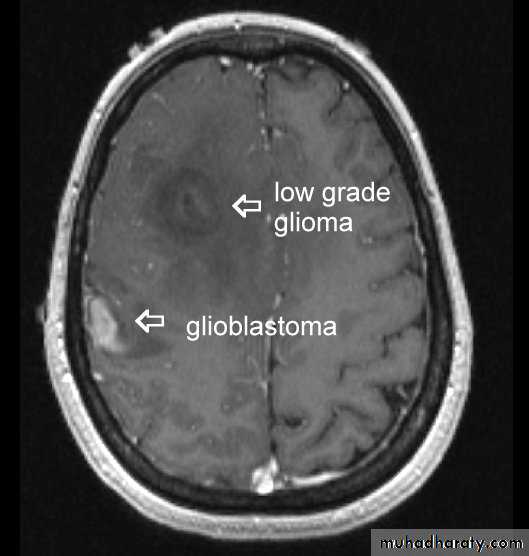

LOW GRADE GLIOMA MRI’S

LOW GRADE GLIOMA AXIAL MRI

GLIOBLASTOMA MULTIFORMI